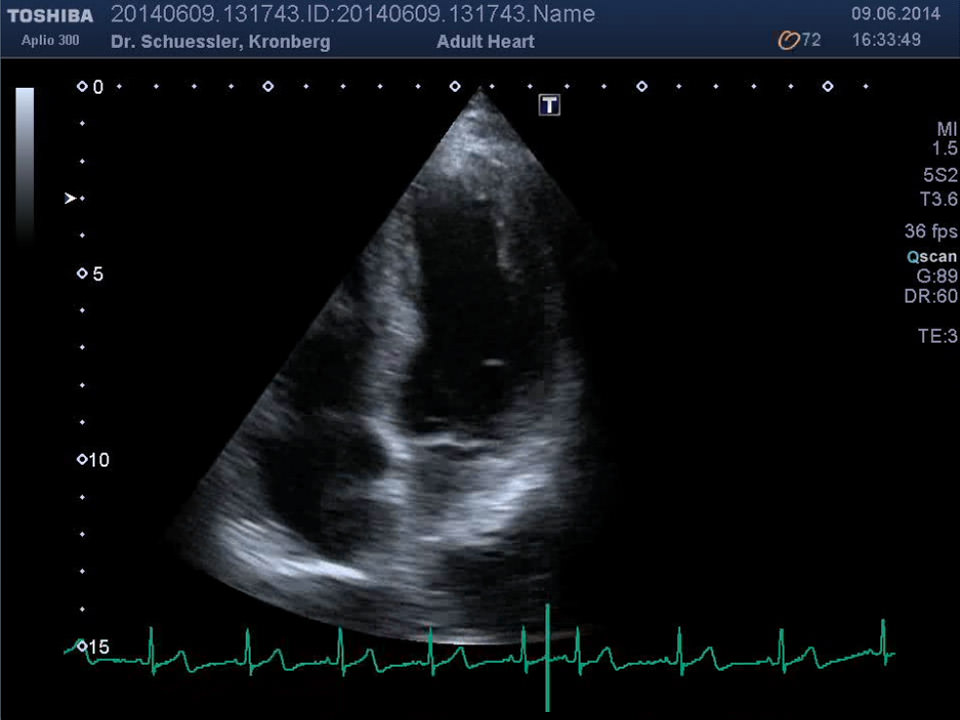

Die Ultraschalluntersuchung des Herzens erlaubt, auf einem nicht belastenden Weg, eine umfangreiche Darstellung des Herzens. Unter Hinzunahme der Farbdopplertechnik kann eine ausführliche Beurteilung der Strukturen und der Funktion des Herzens erfolgen.

• Größe der Herzhöhlen

• Wanddicken des Herzmuskels

• Pumpfunktion des Herzmuskels

• Segmentale Bewegungsstörungen des Herzmuskels als Hinweis auf Durchblutungsstörungen